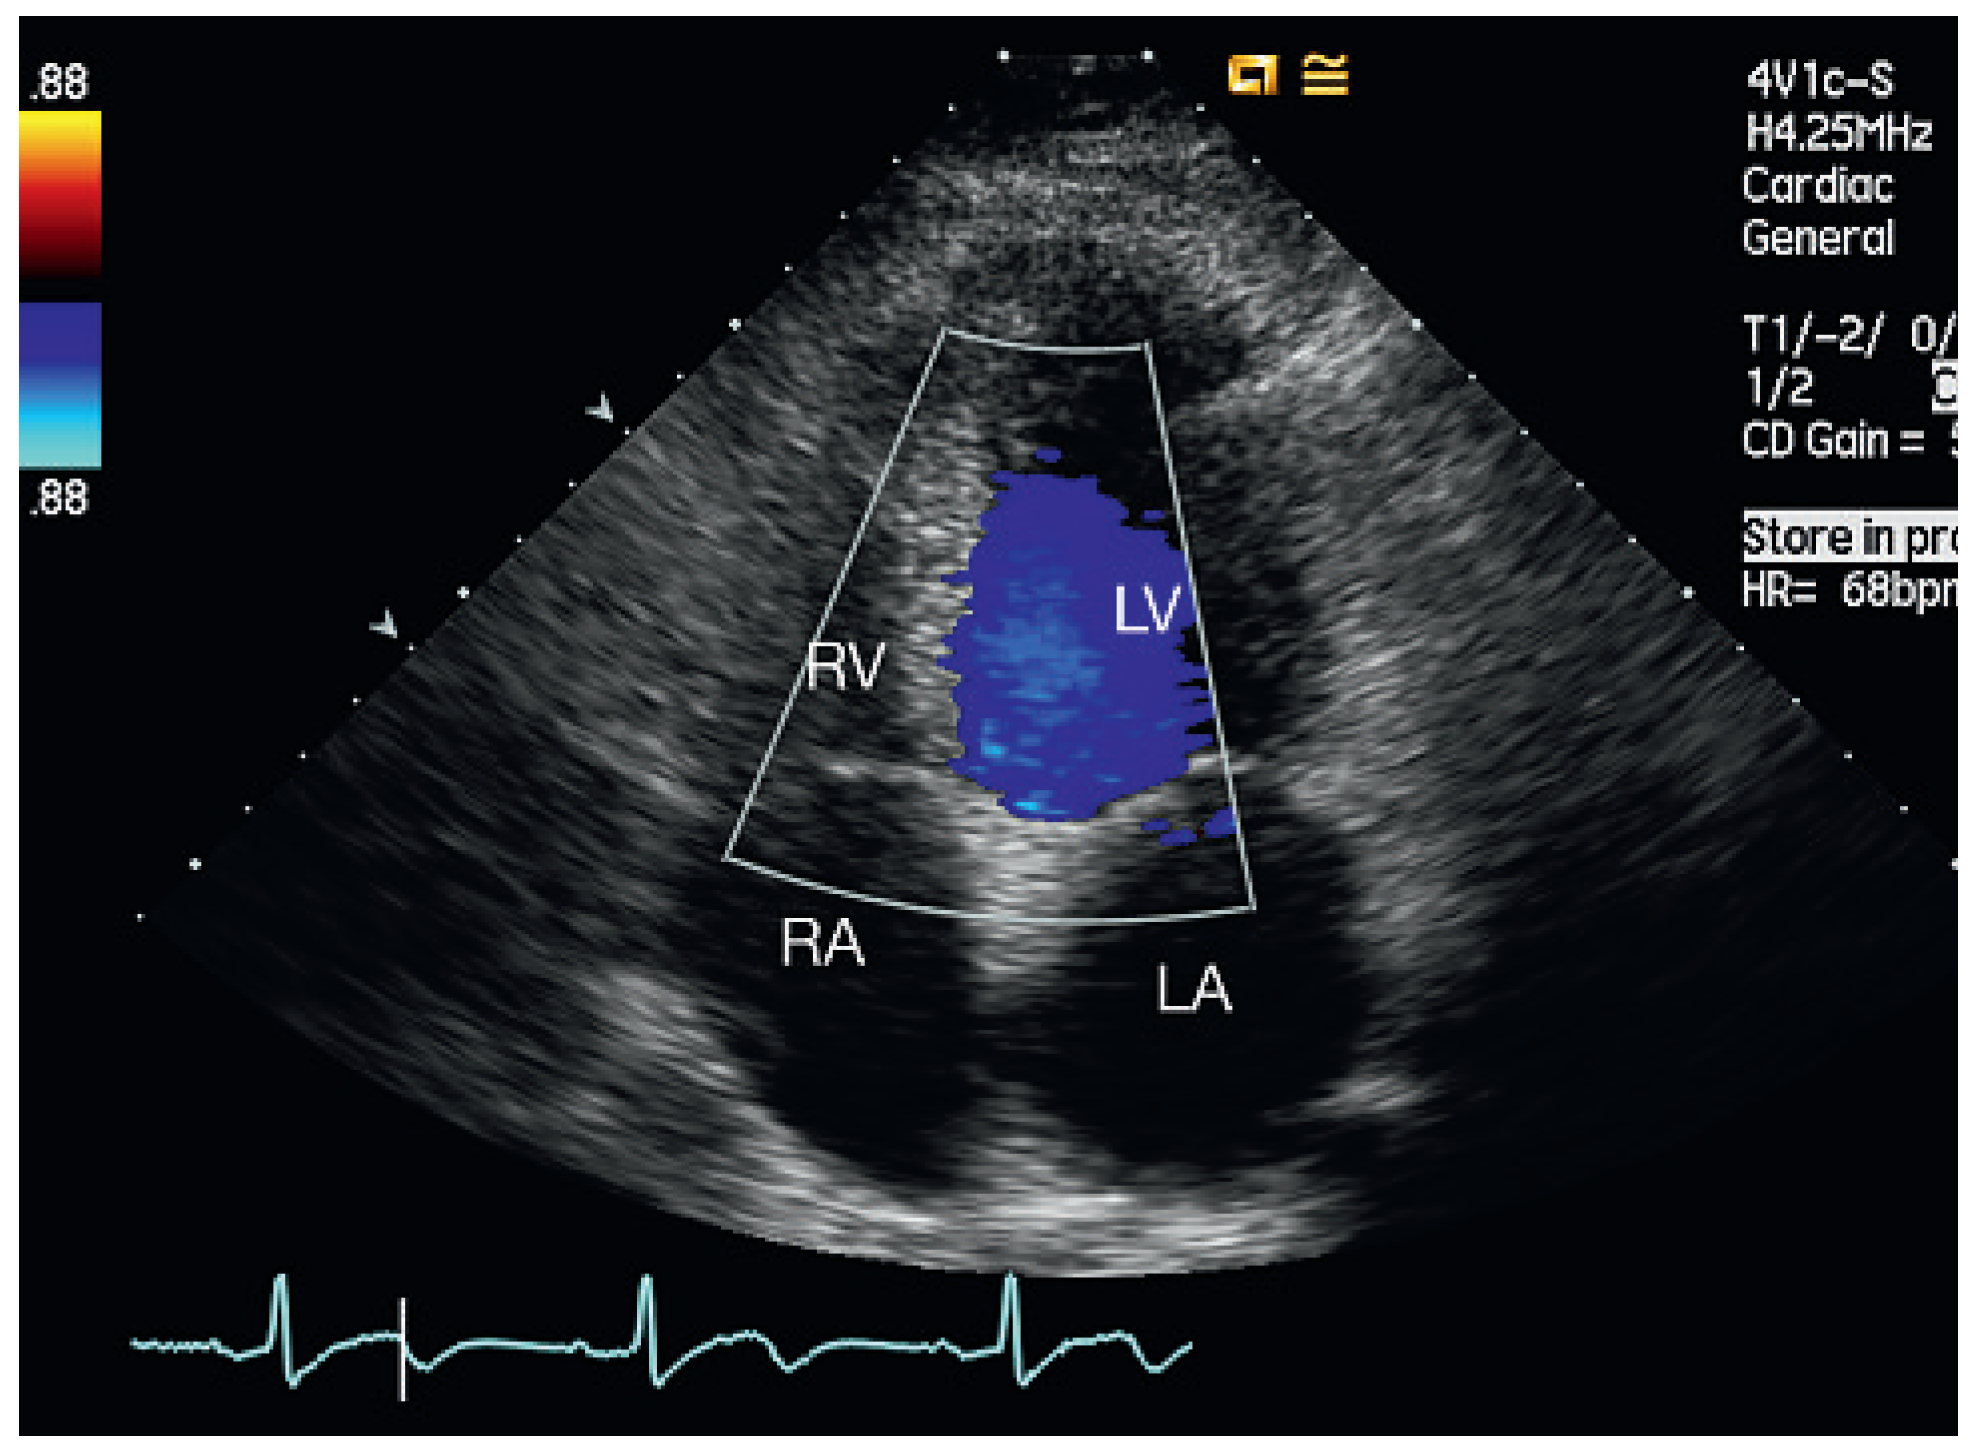

Figure 2.

Patient 1, five months later. Four-chamber view: no evidence of residual VSD. LA = left atrium; LV = left ventricle; RA = right atrium; RV = right ventricle.

Echocardiographic follow-up revealed spontaneous closure of the septal perforation in four of the five patients (Figure 2). In one patient the septal defect persisted for one and a half years after surgery, but he remained asymptomatic without deterioration of left ventricular function or increased pulmonary artery systolic pressure.